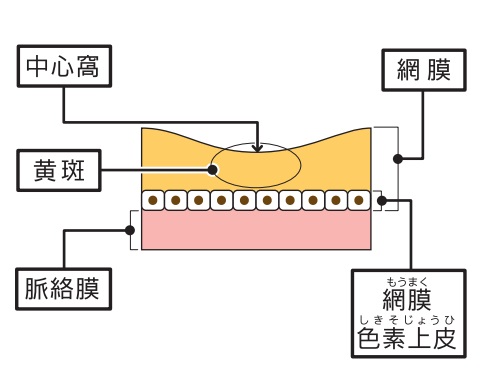

眼の構造と働きについて

私たちが物を見る、つまり外から眼に光が入ったとき、その情報は角膜→瞳孔→水晶体→硝子体と通過していき、最後に網膜に像が結ばれます。そこから視神経を介して情報が脳に伝わり、私たちは「見た」と感じます。 眼は、よくフィルムカメラに例えられます。水晶体がレンズにあたり、網膜はフィルムにあたるという関係ですね。

私たちが物を見る、つまり外から眼に光が入ったとき、その情報は角膜→瞳孔→水晶体→硝子体と通過していき、最後に網膜に像が結ばれます。そこから視神経を介して情報が脳に伝わり、私たちは「見た」と感じます。 眼は、よくフィルムカメラに例えられます。水晶体がレンズにあたり、網膜はフィルムにあたるという関係ですね。

黄斑・中心窩について

黄斑とは、網膜の中心部にあり、視力ともっとも深いかかわりを持っています。物を見たときのその物の大きさや形、奥行きなど、視覚情報の大半が、黄斑で認識されています。ここで障害が起こると、当然ながら視力の低下が引き起こされます。 黄斑のさらに中心には、「中心窩」があります。こちらはさらに重要な部分であり、障害されたときにはより大幅な視力低下を招きます。

黄斑とは、網膜の中心部にあり、視力ともっとも深いかかわりを持っています。物を見たときのその物の大きさや形、奥行きなど、視覚情報の大半が、黄斑で認識されています。ここで障害が起こると、当然ながら視力の低下が引き起こされます。 黄斑のさらに中心には、「中心窩」があります。こちらはさらに重要な部分であり、障害されたときにはより大幅な視力低下を招きます。